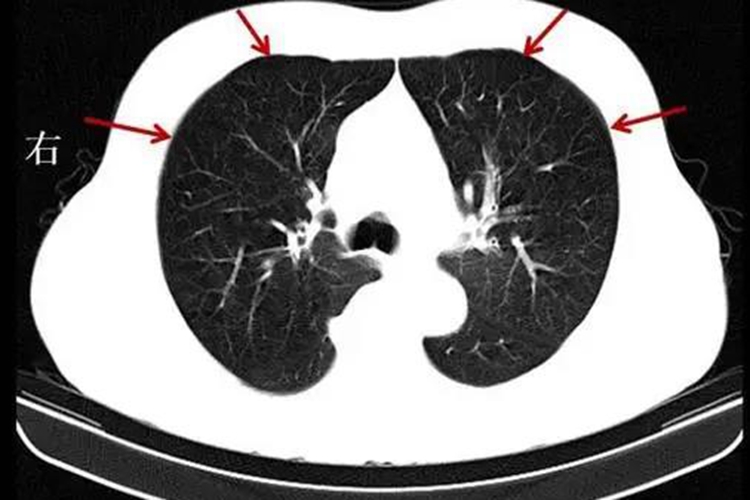

慢阻肺指的是慢性阻塞性肺疾病,是一种常见的慢性呼吸系统疾病,患者往往在饮食上有所顾虑,多数情况下是可以吃豆腐的,但具体食用情况存在个体差异。

慢性阻塞性肺疾病患者是否能吃豆腐,主要取决于个人的身体状况和病情。豆腐作为一种高蛋白、低脂肪的食物,富含大豆异黄酮、大豆蛋白等营养成分,对慢性阻塞性肺疾病患者具有一定的益处。